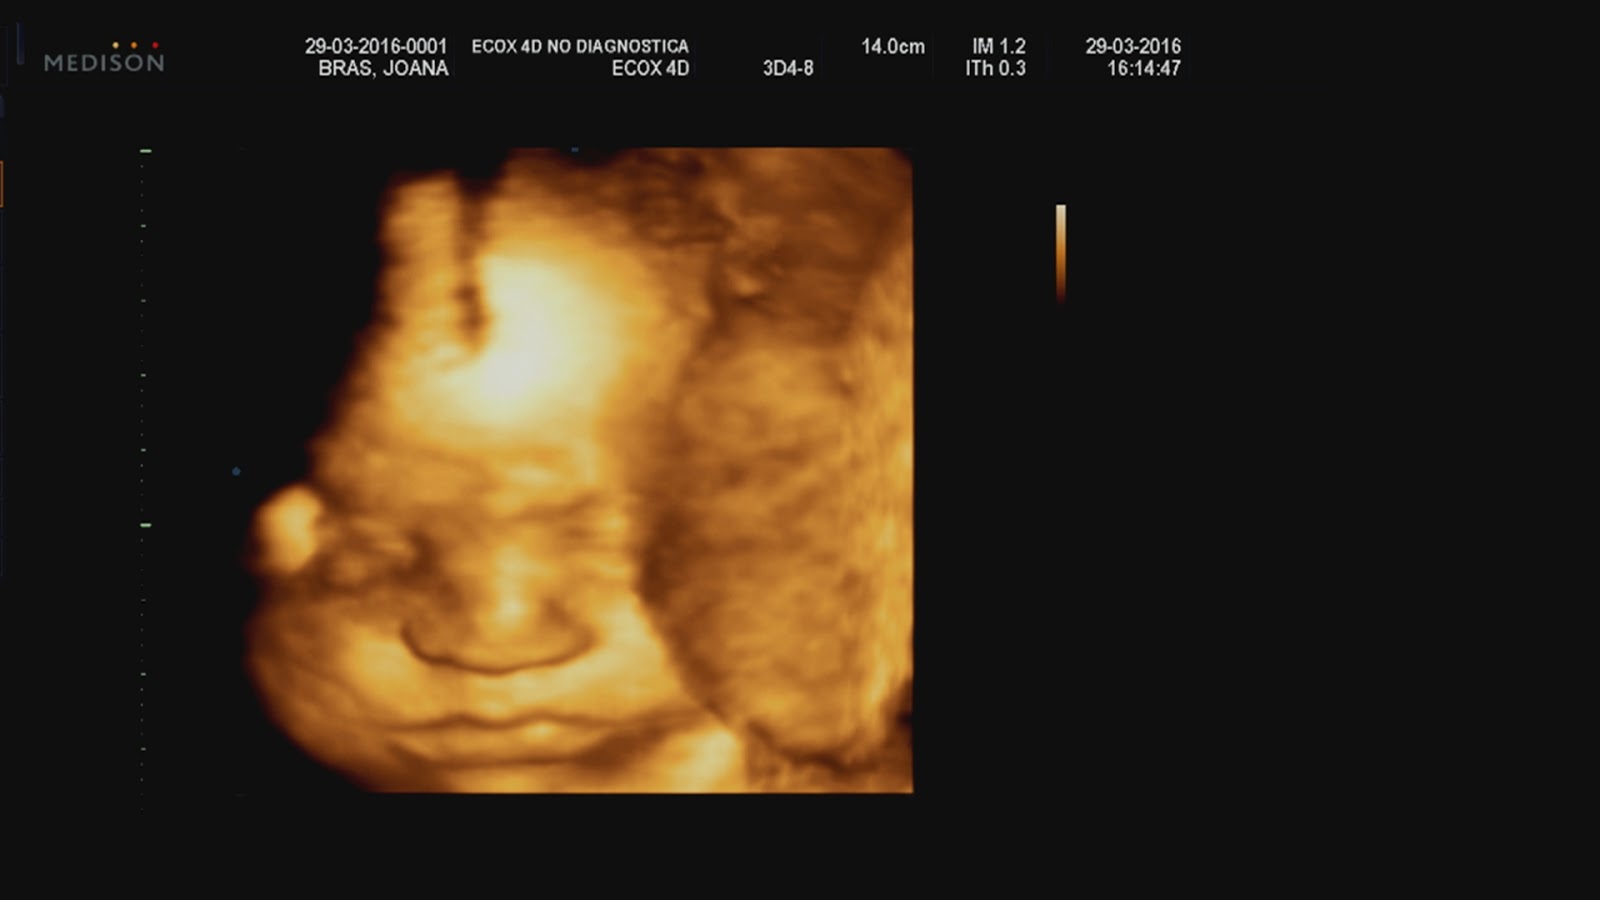

Esta semana fui fazer uma ecografia emocional na Ecox, para conhecer a Luísa. Já tinha feito na altura da Isabel e desta vez fi-lo também. Estava cheia de curiosidade em perceber como seria a carinha dela, mas tinha principalmente curiosidade em vê-la, em tempo real. Sinto-a muito (mexe-se ainda mais do que a Isabel) mas queria vê-la a meter a mão na cara, na boca, espreguiçar-se, o que fosse! Foi isso tudo e muito mais: uma contorcionista, com pés e mãos na cara,  língua de fora, mãozinha debaixo da cara e um sem-número de expressões. É linda (só uma mãe para dizer isto de uma ecografia haha) e parece-me mesmo uma cópia da irmã: nariz abatatado, boquinha, queixo pequeno.